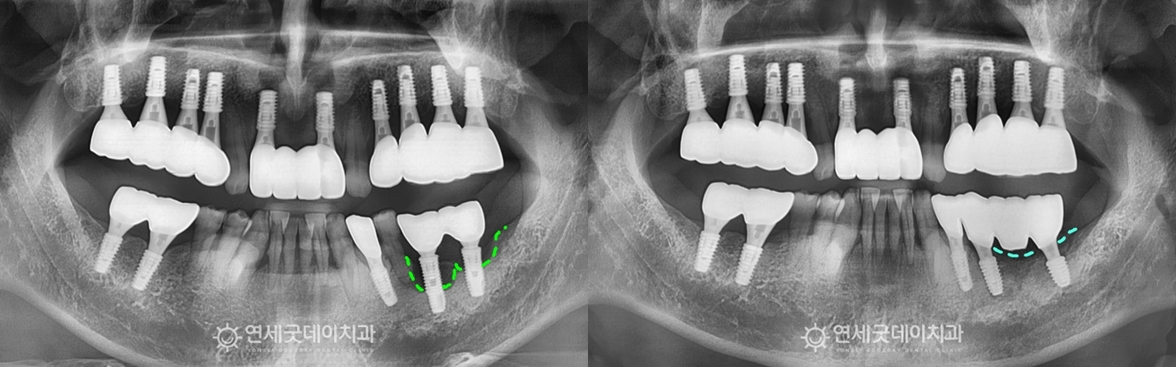

엑스레이를 보면 #35 부위에 치근단 병소가 확인되었고,

치근단염이 관찰되었던 #35 부위를 발치 및 제거 후에는 추후 새로운 임플란트를 안전하게 심고,

치료전과 후를 보시면 완전히 내려 앉았던 잇몸뼈가